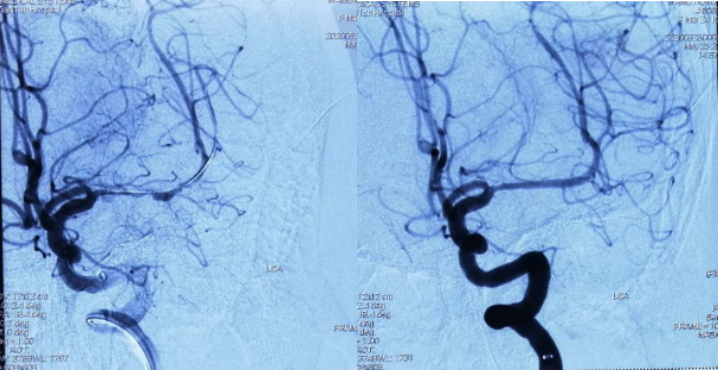

2020.5 DSA左侧大脑中动脉重度狭窄

介入治疗后明显改善

DSA(天坛医院-2021.03.17 MCA支架内重度狭窄

赛诺球囊扩张后狭窄有所改善但管壁不光滑

药物球囊扩张(2.0 mm×20 mm)

药物球囊扩张后

药物球囊扩张后10分钟狭窄明显改善且血管壁较光滑